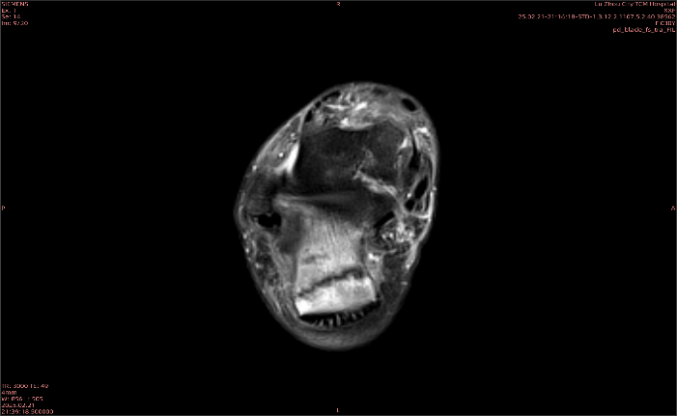

隱性骨折在MRI表現(xiàn)為T(mén)1WI序列上見(jiàn)由關(guān)節(jié)面向骨干走行的形態(tài)各異低信號(hào)區(qū),有線狀、條狀、紊亂低信號(hào),信號(hào)強(qiáng)度不均勻。與T1WI低信號(hào)改變相對(duì)應(yīng)部位在T2WI上表現(xiàn)為相應(yīng)形狀的高、低混雜信號(hào),且部分低信號(hào)周?chē)梢?jiàn)高信號(hào)水腫改變。STIR序列圖像上病灶呈顯著高信號(hào),與信號(hào)被抑制的臨近正常骨髓形成鮮明對(duì)比,分界也較T2WI成像更為清楚。脂肪組織抑制技術(shù)是MRI的一個(gè)重要性能,脂肪抑制技術(shù)在MRI應(yīng)用中可以改善組織對(duì)比和增加病變顯示機(jī)會(huì),這樣骨髓的脂肪抑制后就不會(huì)有任何信號(hào),而隱性骨折線及骨髓水腫的異常高信號(hào)就會(huì)更加明顯的顯示出來(lái)。

舉例圖像

圖1

專(zhuān)業(yè)解釋看不懂沒(méi)關(guān)系,大家看圖1和圖2就可以了,這是同一個(gè)患者跟骨的磁共振和CT圖像,圖1的紅色箭頭指示的黑線就是磁共振圖像顯示的骨折線,一目了然。而對(duì)比圖2的CT圖像上并未顯示異常。